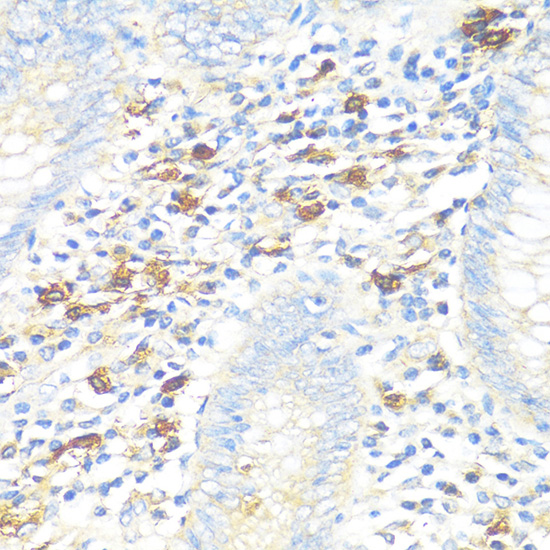

Immunohistochemistry of paraffin-embedded Human appendix using TPSAB1 at dilution of 1:100 (40x lens).